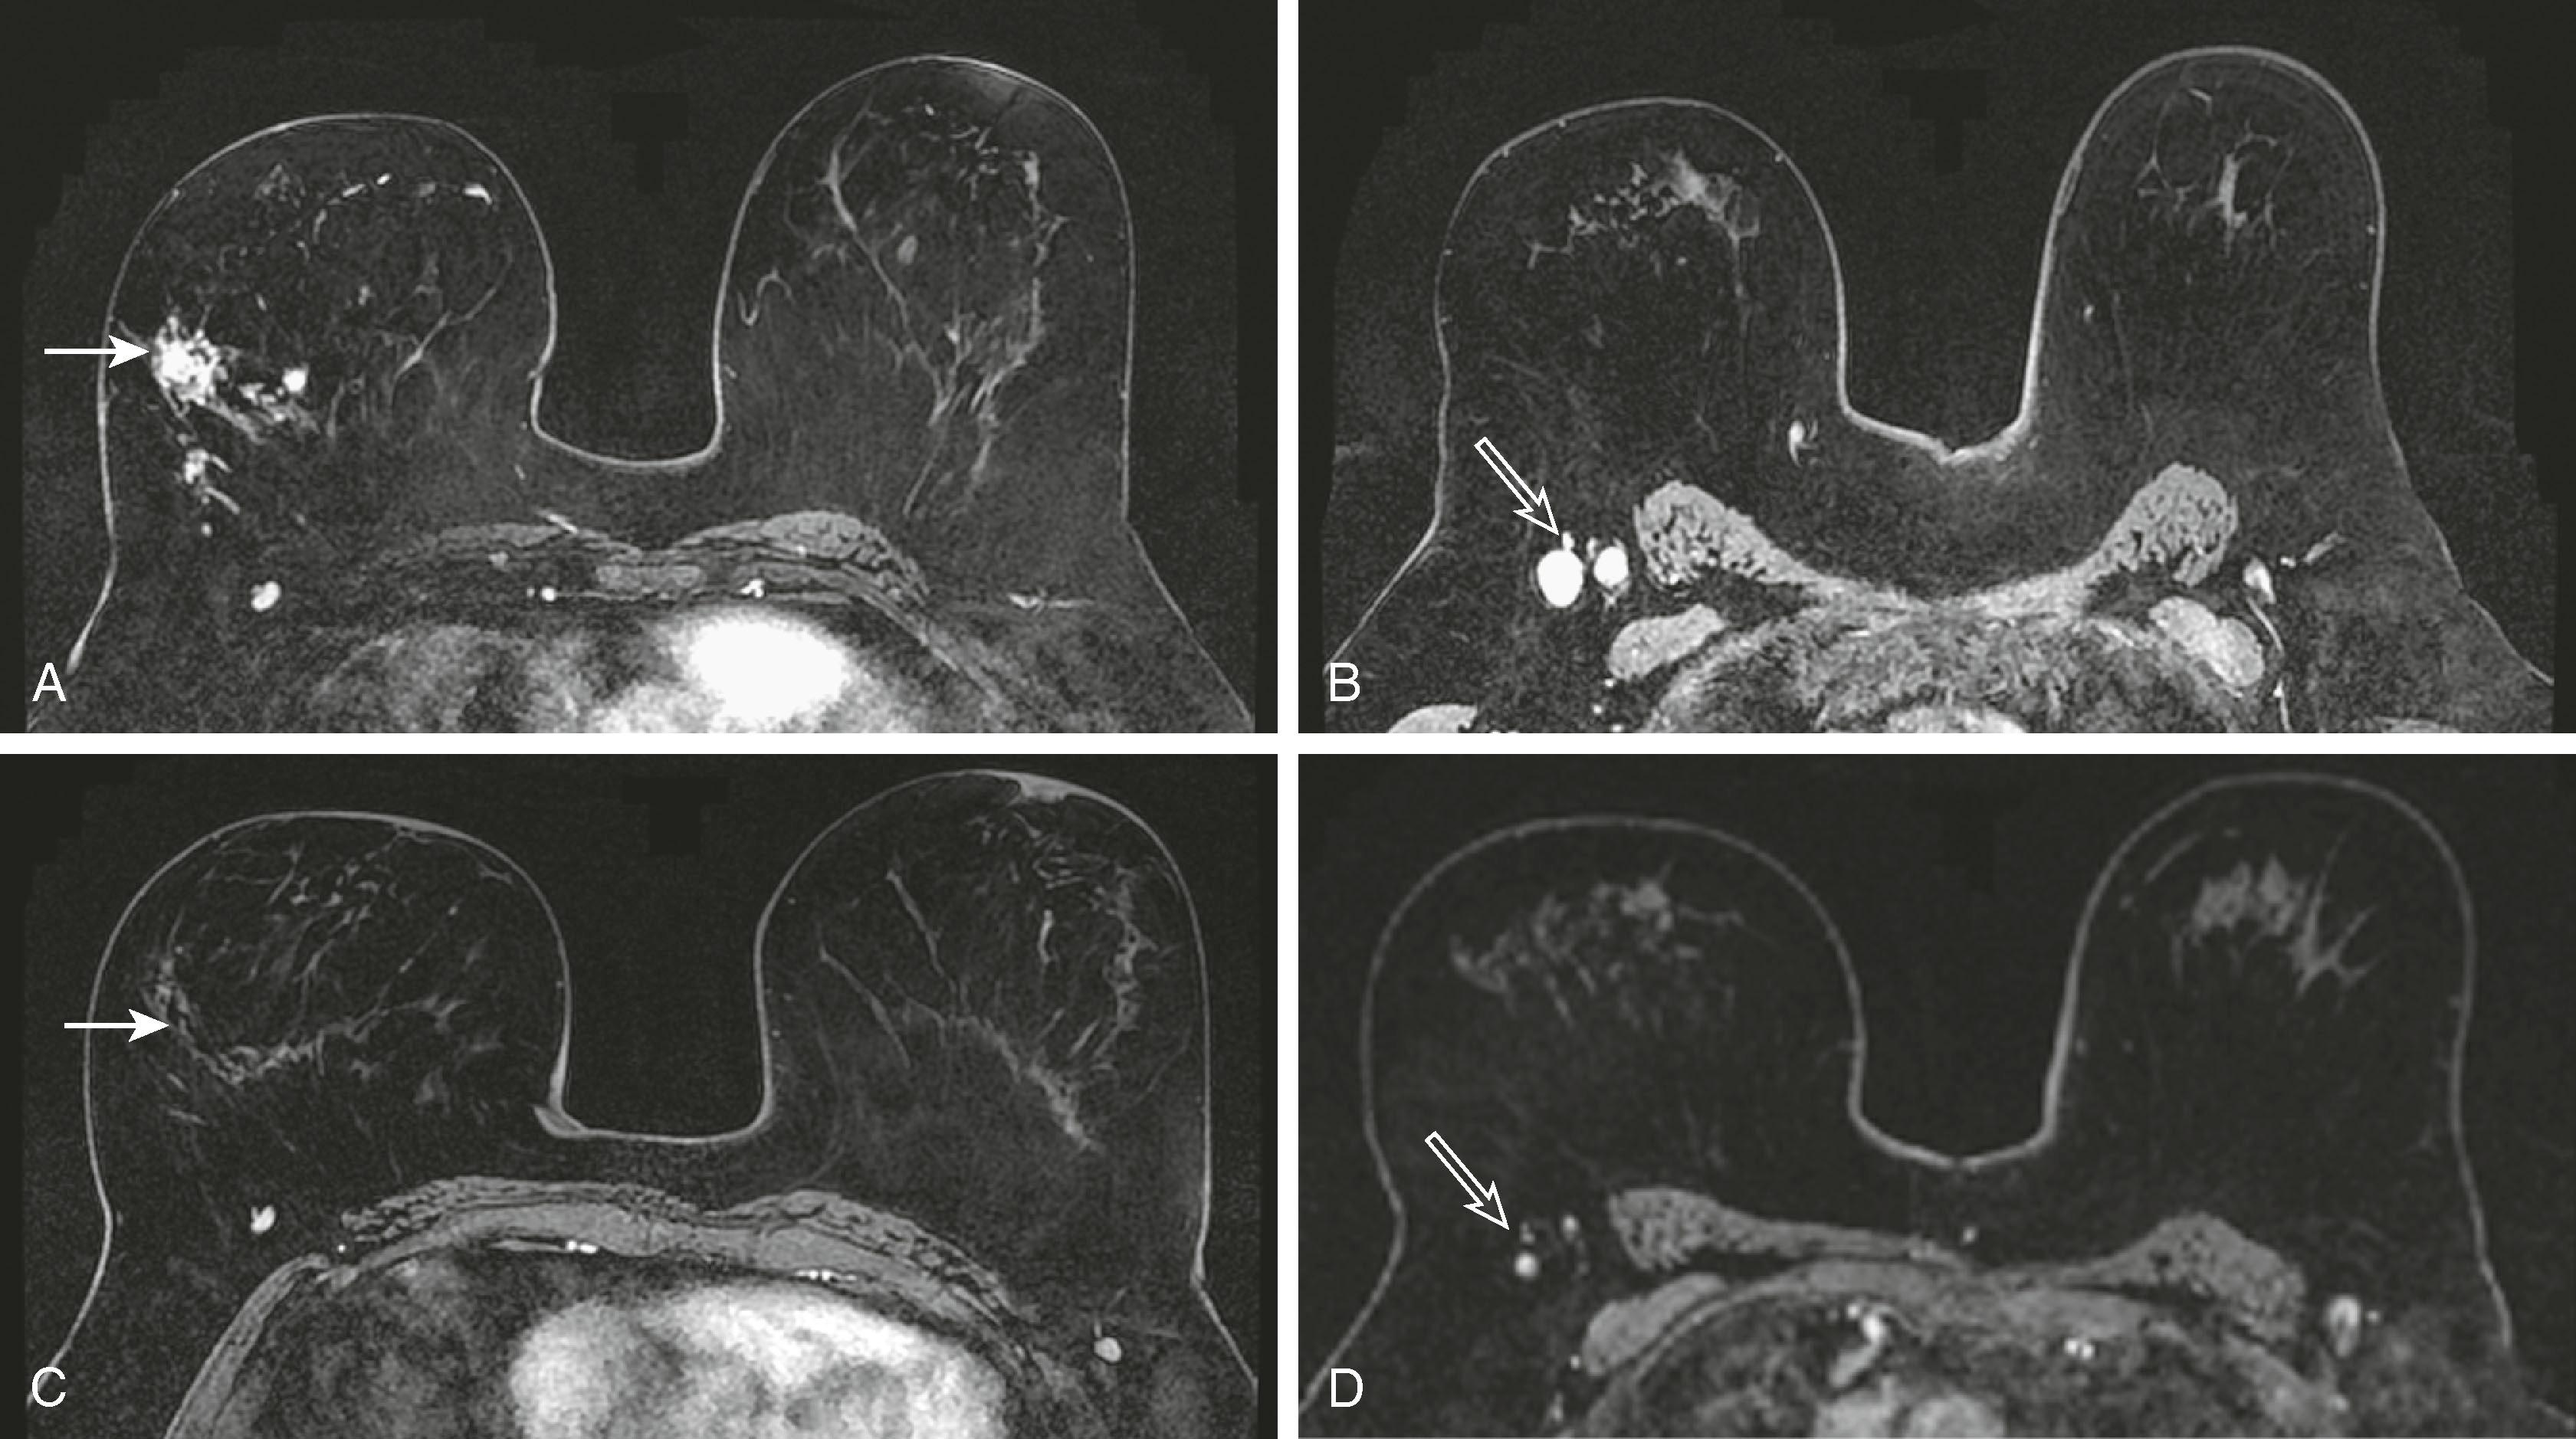

MRI is useful for following the response of tumors to neoadjuvant chemotherapy . Mammography, ultrasound, and physical examination are notoriously inaccurate in evaluating the response to chemotherapy. MRI and PET have proved to be superior in this regard. Kuhl reported that MRI findings have been shown to correlate better with tumor response than conventional imaging, with correlation coefficients ranging between 0.72 and 0.93 versus 0.30 and 0.52. One important caveat is that MRI, although very sensitive for detecting macroscopic invasive cancer, cannot exclude residual microscopic disease or low-grade DCIS. Although the MRI appears negative, there may be tumor remnants in 30% of patients. Interestingly, the underestimation is greater for patients who have a complete MRI response to chemotherapy than for patients who have a partial or no response. Fig. 8.31 demonstrates a complete MRI response to chemotherapy in a patient with lobular carcinoma. Fig. 8.32 demonstrates a patient with a partial response to chemotherapy. The tumor diminished in size with only several residual foci of tumor, and the kinetic pattern changed from plateau to progressive.

Fig. 8.31, Patient with a history of lobular carcinoma ( solid arrow in A ) and enlarged right axillary lymph nodes ( open arrow in B ). After the administration of neoadjuvant chemotherapy, all magnetic resonance imaging evidence of the tumor ( solid arrow in C ) and lymphadenopathy ( open arrow in D ) disappears.